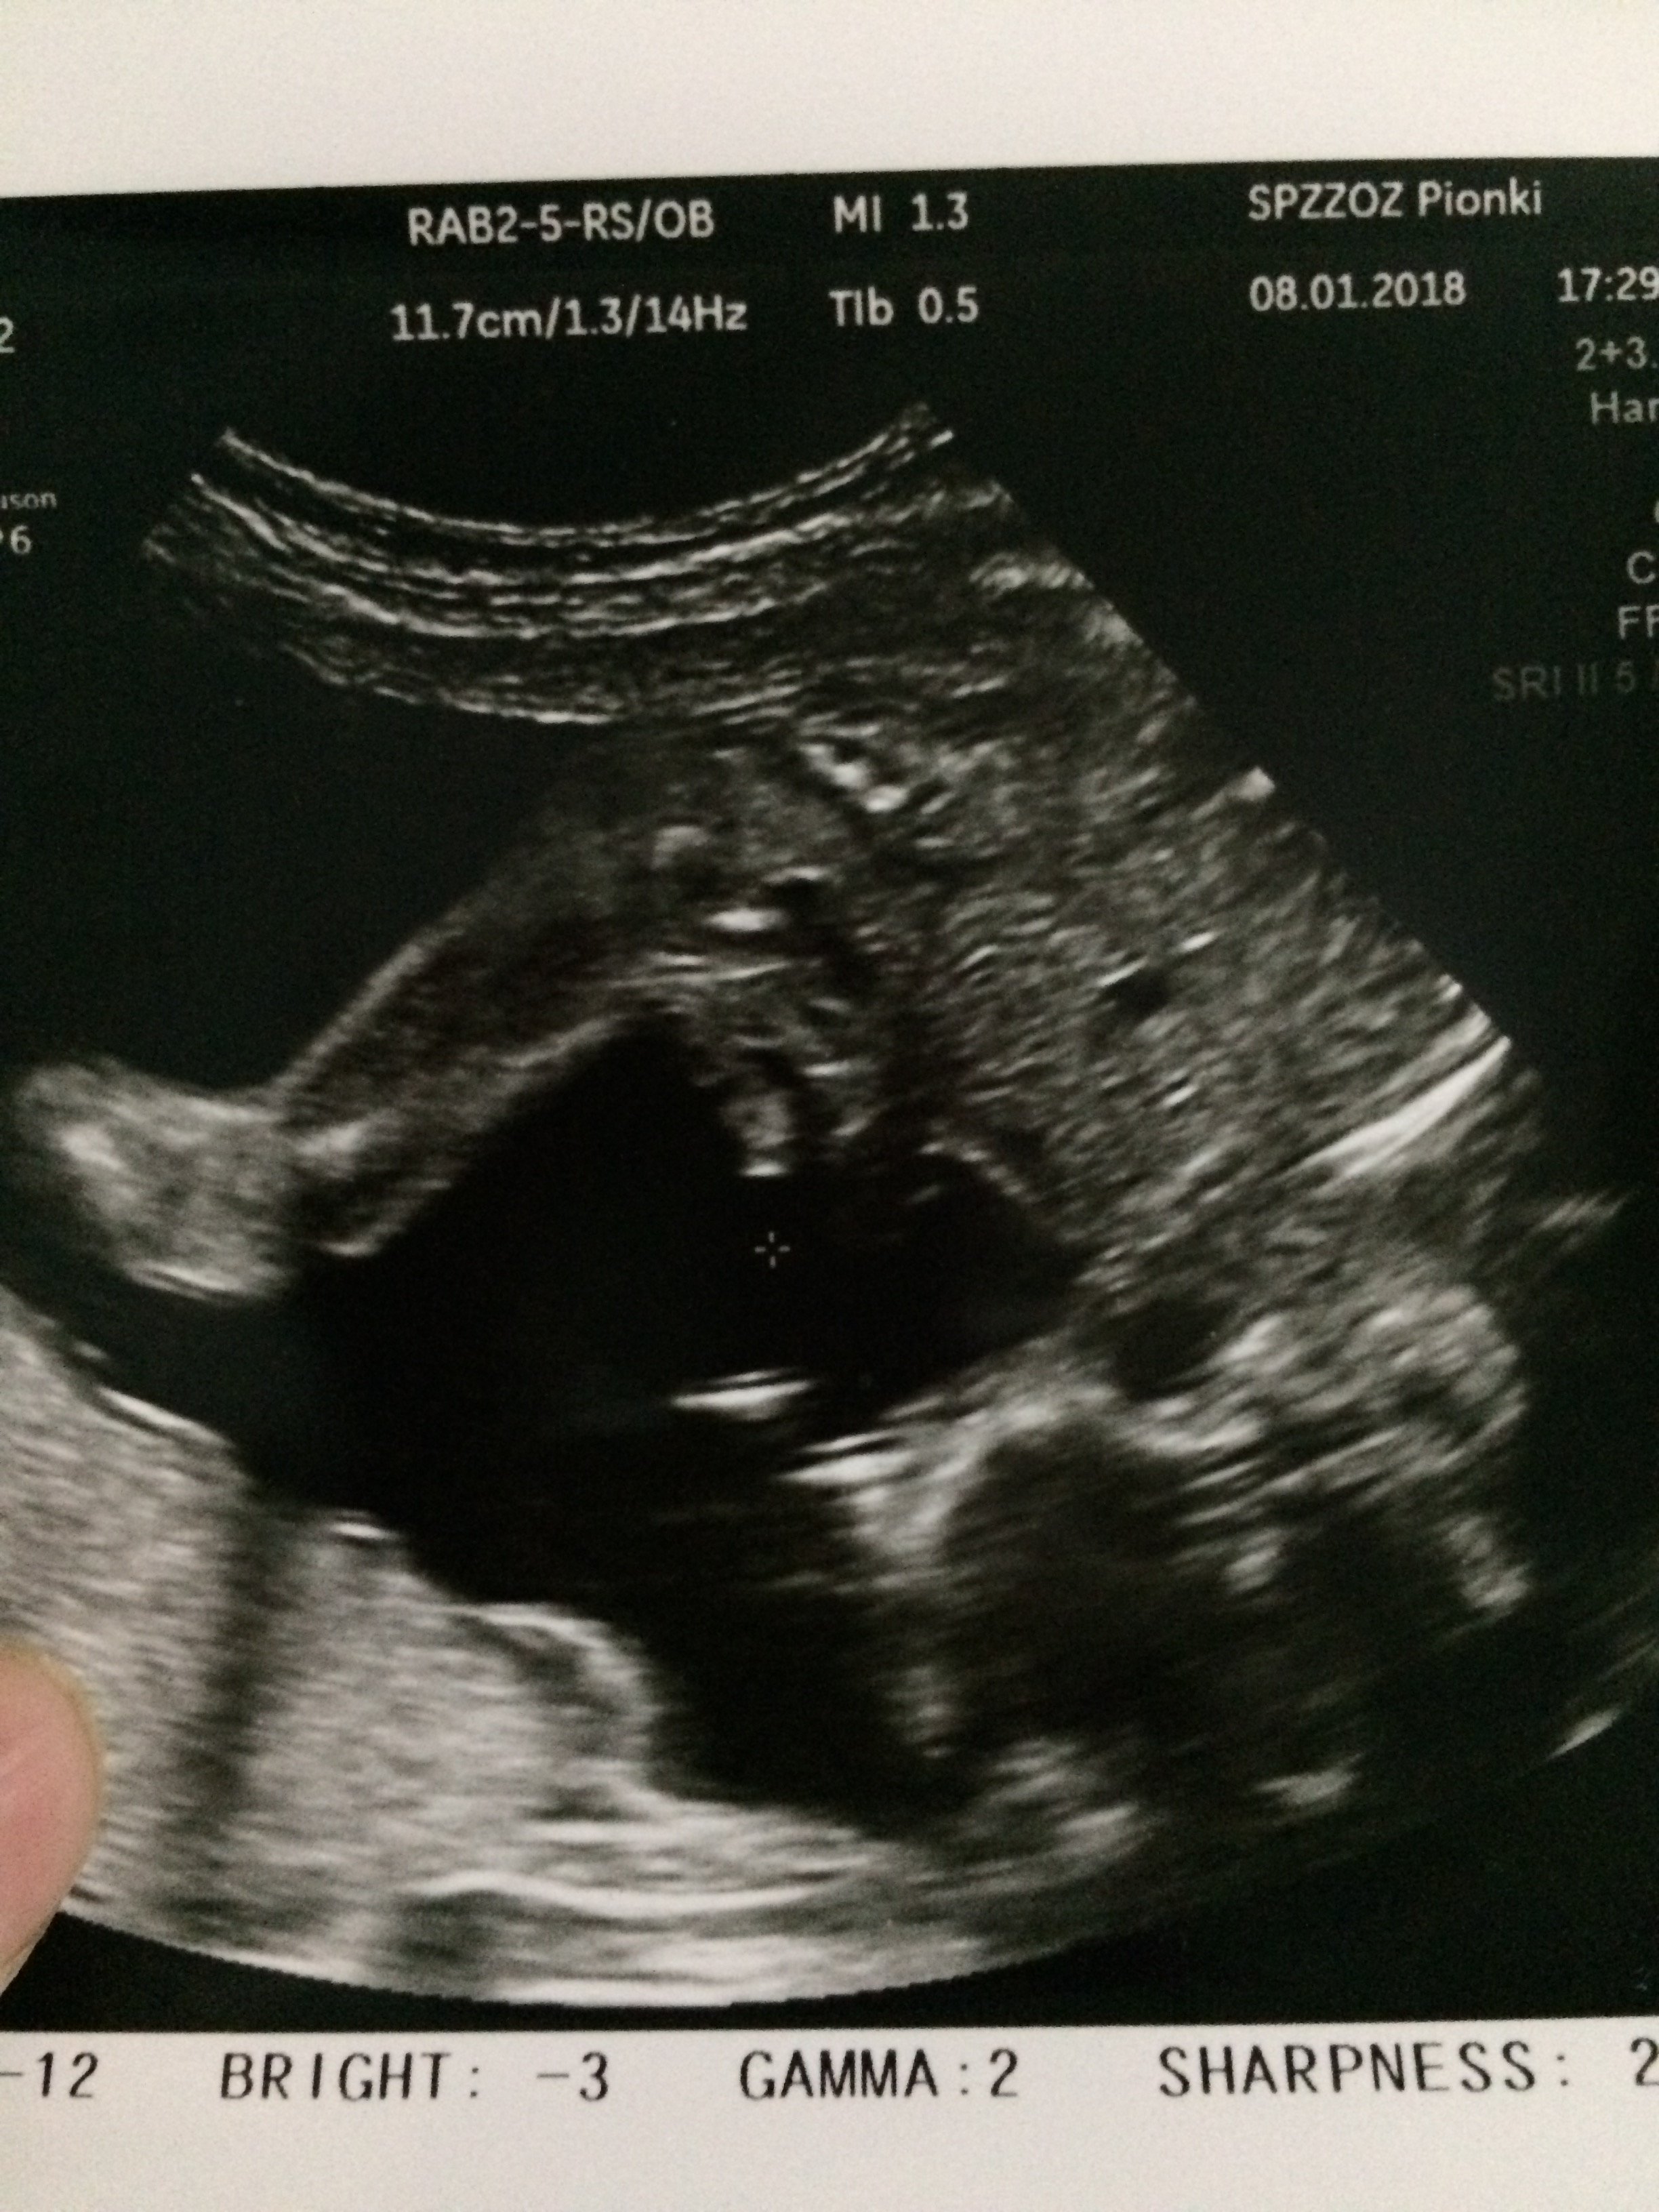

Cześć dziewczyny proszę was o ocenę zdjęcia usg... Miesiąc temu zapowiedzieli mi syna a 4 grudnia na połówkowym ze córka... Trochę mam mętlik w głowie 😞

20tc, lekarz na 100% pewny...

Na zbliżonym zdjęciu ponoć widać jak na talerzu, że to... ;) no właśnie, chłopak czy dziewuszka?